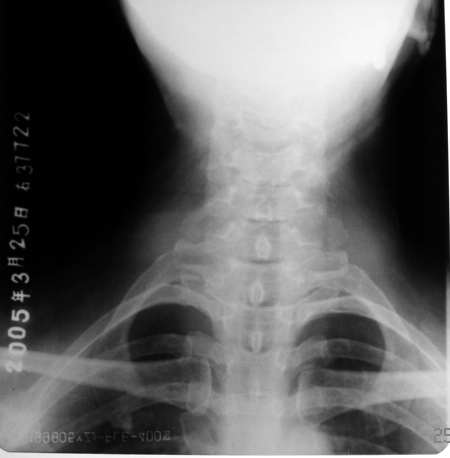

标题: X0220:颈椎 正常还是变异

女 55岁 颈部不适一周余

第七颈肋.

第七颈肋

正常的吧,没有颈肋啊。

无第七颈肋,正常.[emb10]

是颈肋!相片不是很清楚.

颈7横突(右侧)过长,考虑颈肋。

第7椎右缘影系伪影(头发辫子)大家仔细看:从左上斜向右下都有这样的影象喔!

确实有颈肋不过发育的较短小而已。

每个锥体前侧全透亮啊 没见过

谢谢向医生,本人以为椎前缘类圆形透光区存在“问题”,但现在想可能因投照关系,横突相重所致。[emb18]

第7颈椎横突不长,谈何颈肋